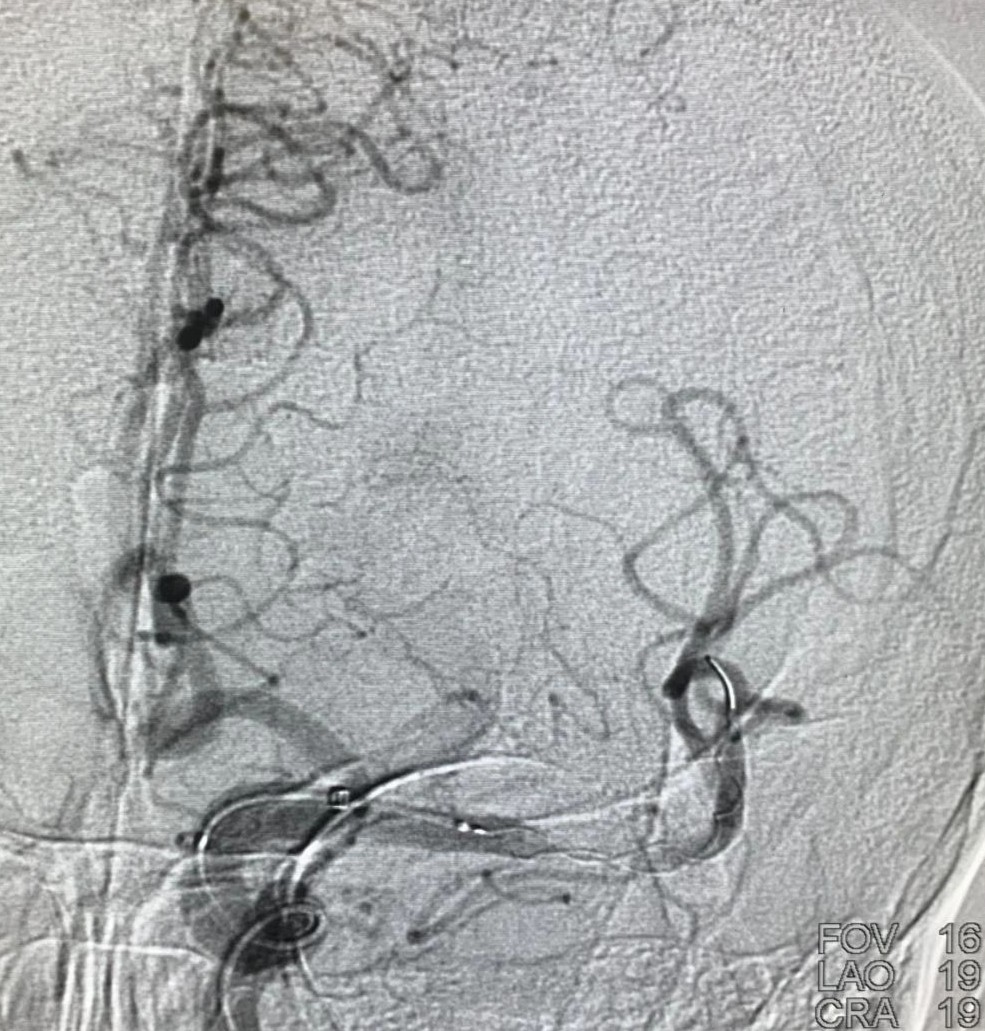

术后造影,mTICI分级III。

术后即刻查体:神志嗜睡,完全性失语,不全性右侧凝视,右侧鼻唇沟浅,右侧上肢肌力1级,下肢肌力2级,NIHSS评分18分。

术后5天查体:神志清楚,运动性失语,右侧鼻唇沟浅,右侧肢体上肢肌力3级、下肢4级,NIHSS评分8分。

三、目前两例使用加奇申翼®取栓器,病人均快速获得血管再通,其中第二例病人一次取栓则完全再通,两例病人均无明显并发症。